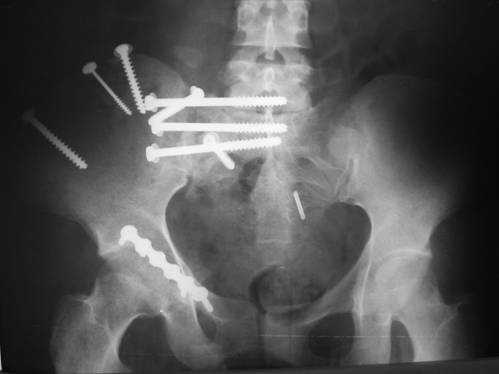

23.09.2003. Одновременный остеосинтез переднего и заднего тазовых полуколец

Результат через 10 дней

и 8месяцев после операции

> Результат через 10 дней и 8месяцев после операции

Да, забыл сказать - отличная работа, искренне восхищаюсь. Кость рубите по Judet (немного не разобрался по рисунку)?

Это наблюдение 5-летней давности тогда кровопотеря составила 2,5 литра. В настоящий момент мы теряем не более 0,7-1,5 литров при одностороннем повреждении и около 2,5-3 литров тогда, когда речь идет о двусторонних повреждениях. Клинический пример.